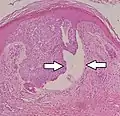

Nodular basal-cell carcinoma (also known as "classic basal-cell carcinoma") accounts for between 50% and 80% of all BCC.[2] It most commonly occurs on the sun-exposed areas of the head and neck.[2] Histopathology shows aggregates of basaloid cells with well-defined borders, showing a peripheral palisading of cells and one or more typical clefts.[17] Such clefts are caused by shrinkage of mucin during tissue fixation and staining.[18] Central necrosis with eosinophilic, granular features may be also present, as well as mucin. The heavy aggregates of mucin determine a cystic structure. Calcification may be also present, especially in long-standing lesions.[17] Mitotic activity is usually not so evident, but a high mitotic rate may be present in more aggressive lesions.[17] Adenoidal BCC can be classified as a variant of NBCC, characterized by basaloid cells with a reticulated configuration extending into the dermis.[17]

Cleft.